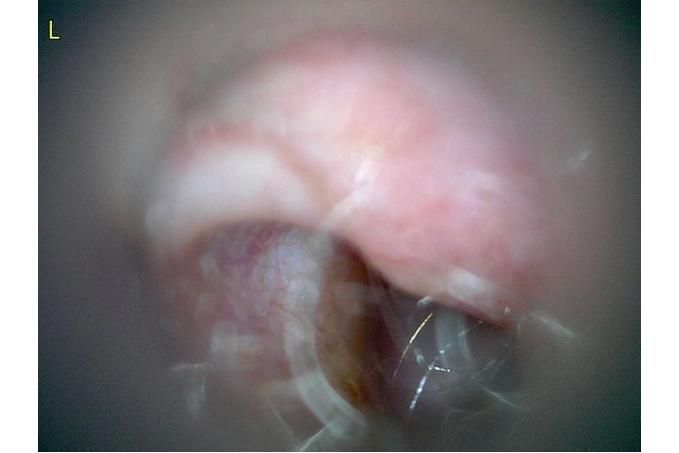

사진만 보고 확진할 수는 없지만 지금 올려주신 귀는 적어도 오른쪽은 정상으로 보이기 어렵습니다 왼쪽은 비교적 연분홍에 가까워 보이지만 오른쪽은 털과 분비물이 많이 차 있고 피부가 자극받은 듯한 모습이라 외이염 가능성을 먼저 생각하게 됩니다 그리고 질문자님이 적어주신 머리 털기 하루 여러 번 귀 만질 때 통증 솜만 닿아도 예민함 귀 긁기 같은 증상은 외이염에서 흔한 신호입니다